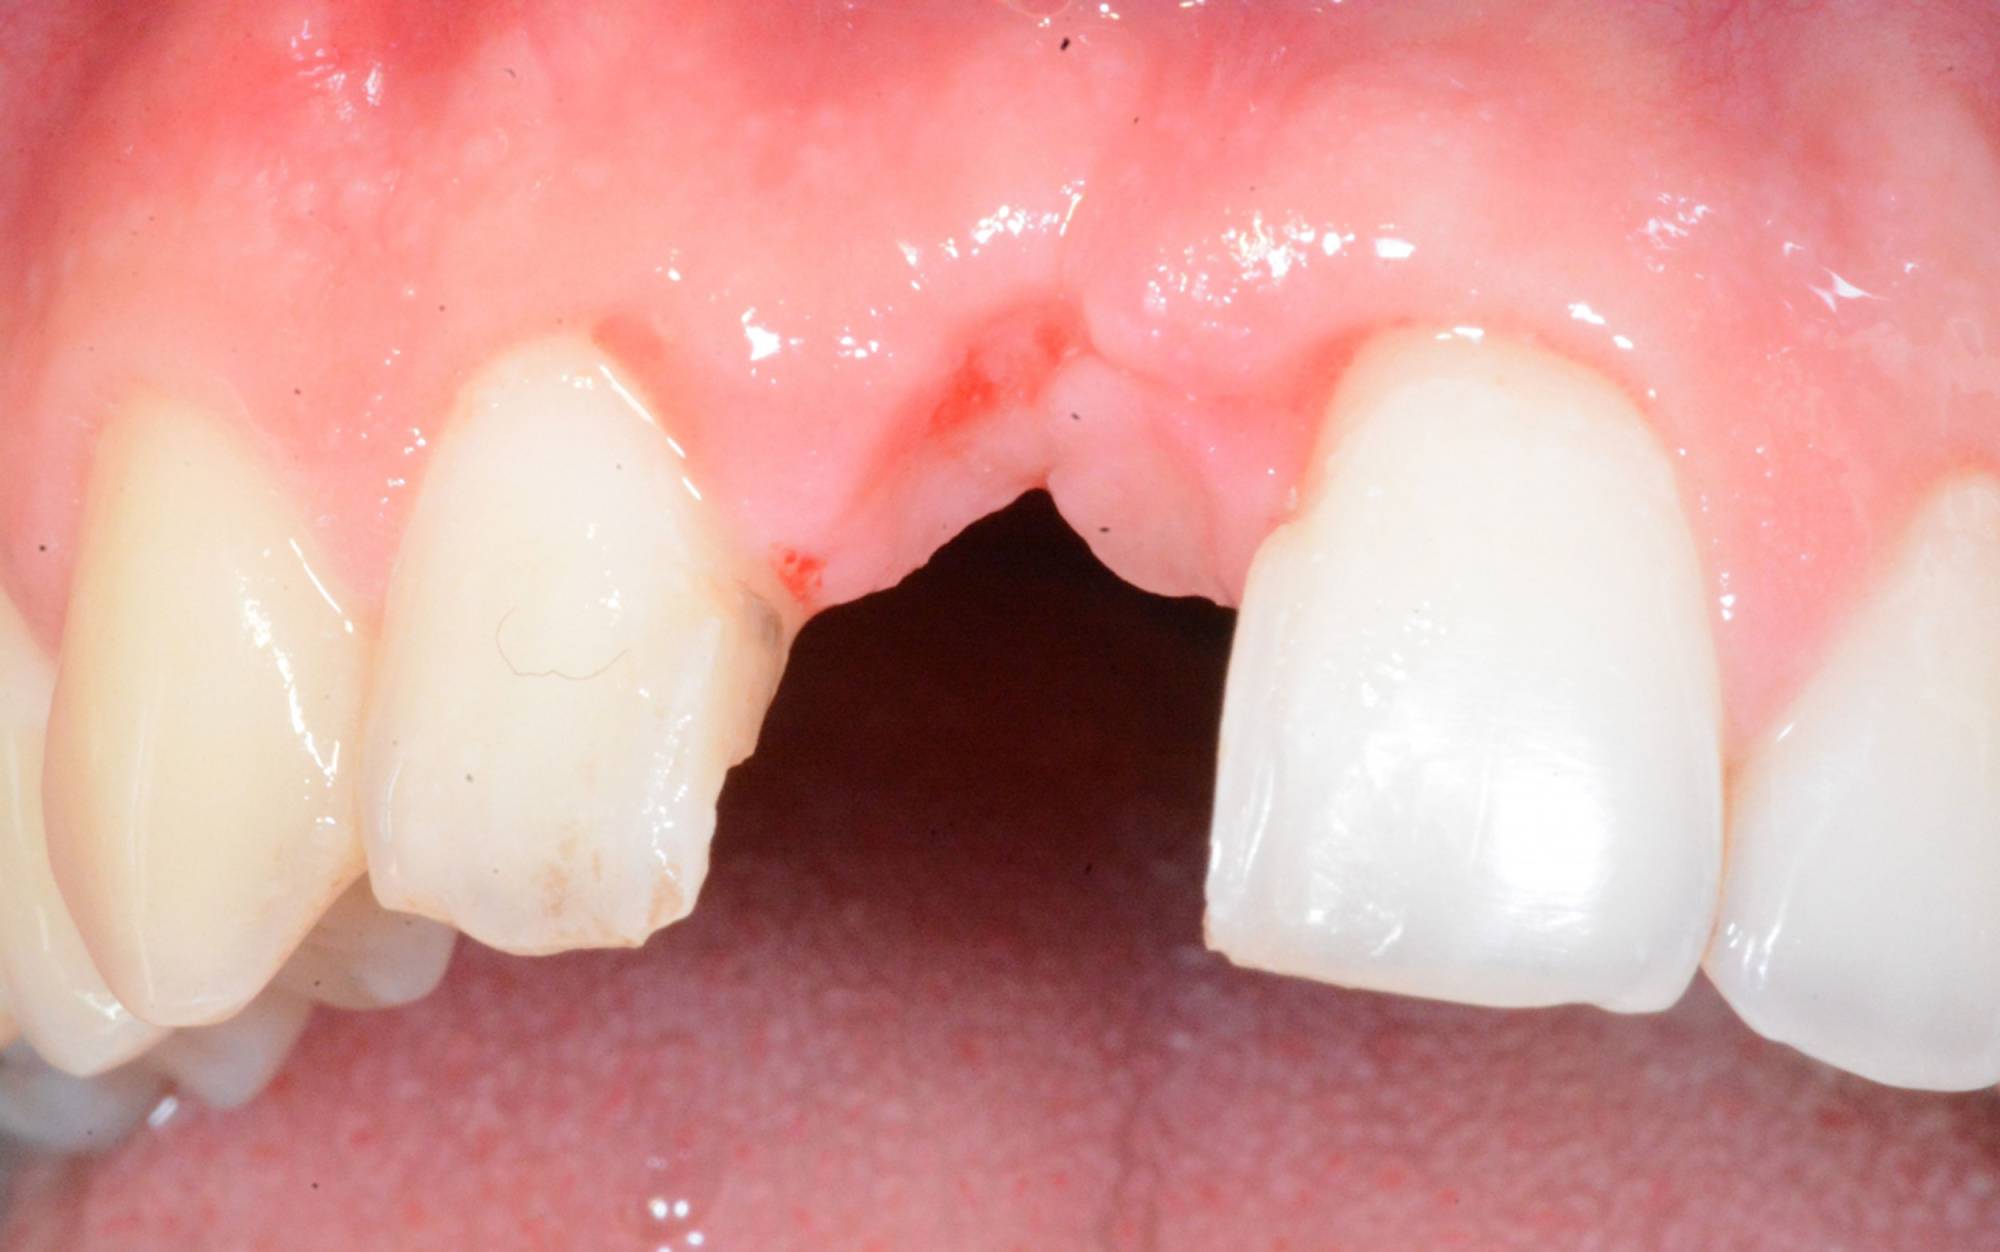

L'impianto dentale osteointegrato è una sorta di radice artificiale che si inserisce nell’osso del paziente, per rimpiazzare un dente mancante.

Quasi tutti possono ricorrere agli impianti, poiché sono una soluzione che presenta solo poche controindicazioni di carattere generale. Anche nei casi in cui non vi sia una sufficiente quantità d’osso per inserire l’impianto, è possibile ricorrere a tecniche di rigenerazione ossea guidata utilizzando biomateriali specifici e porzioni d'osso prelevate dal paziente stesso, per ricostruire la parte ossea mancante.

Generalmente devono trascorrere alcuni mesi tra l’intervento chirurgico di inserimento di un impianto e la realizzazione della protesi da fissare ad esso.